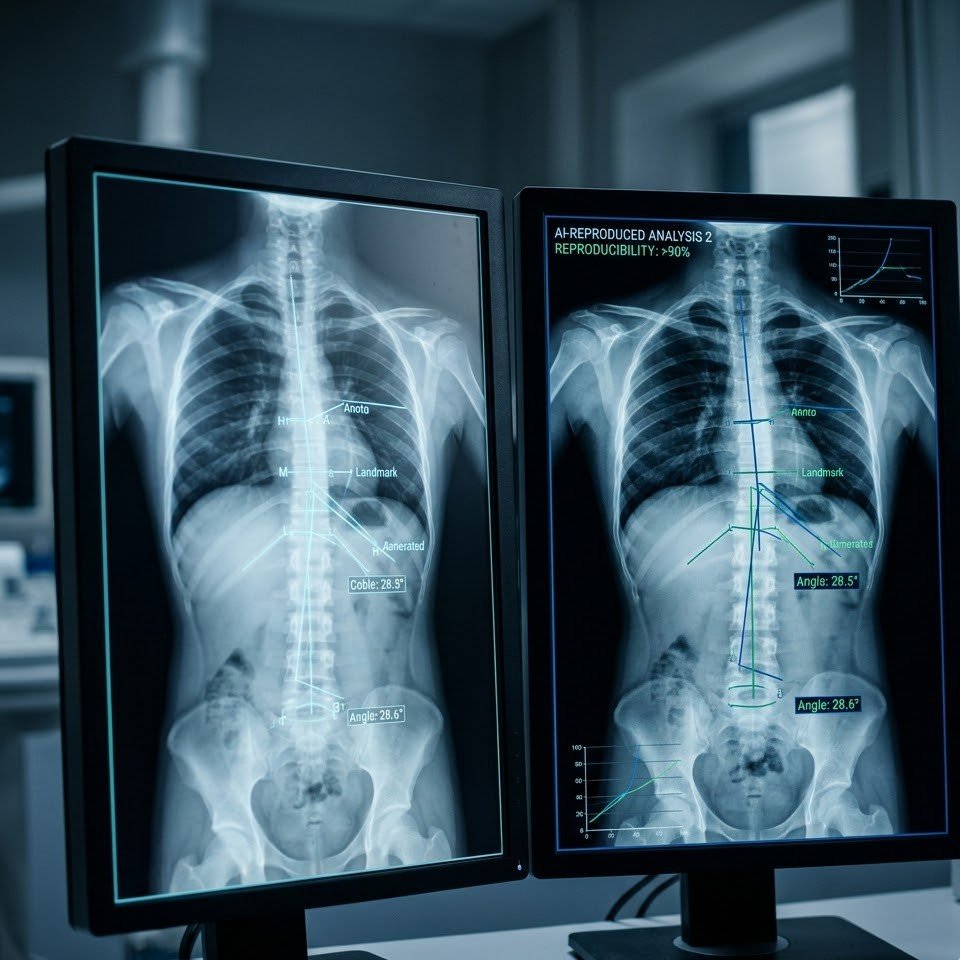

Accurate & Consistent Results

Achieves >90% reproducibility comparable to consultant measurements, while being EHR-agnostic and easy to integrate into clinical workflows.